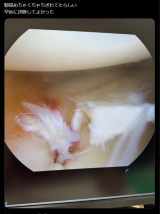

- これは痛そう!平本のちぎれた靭帯(@renhiramotoXXより)